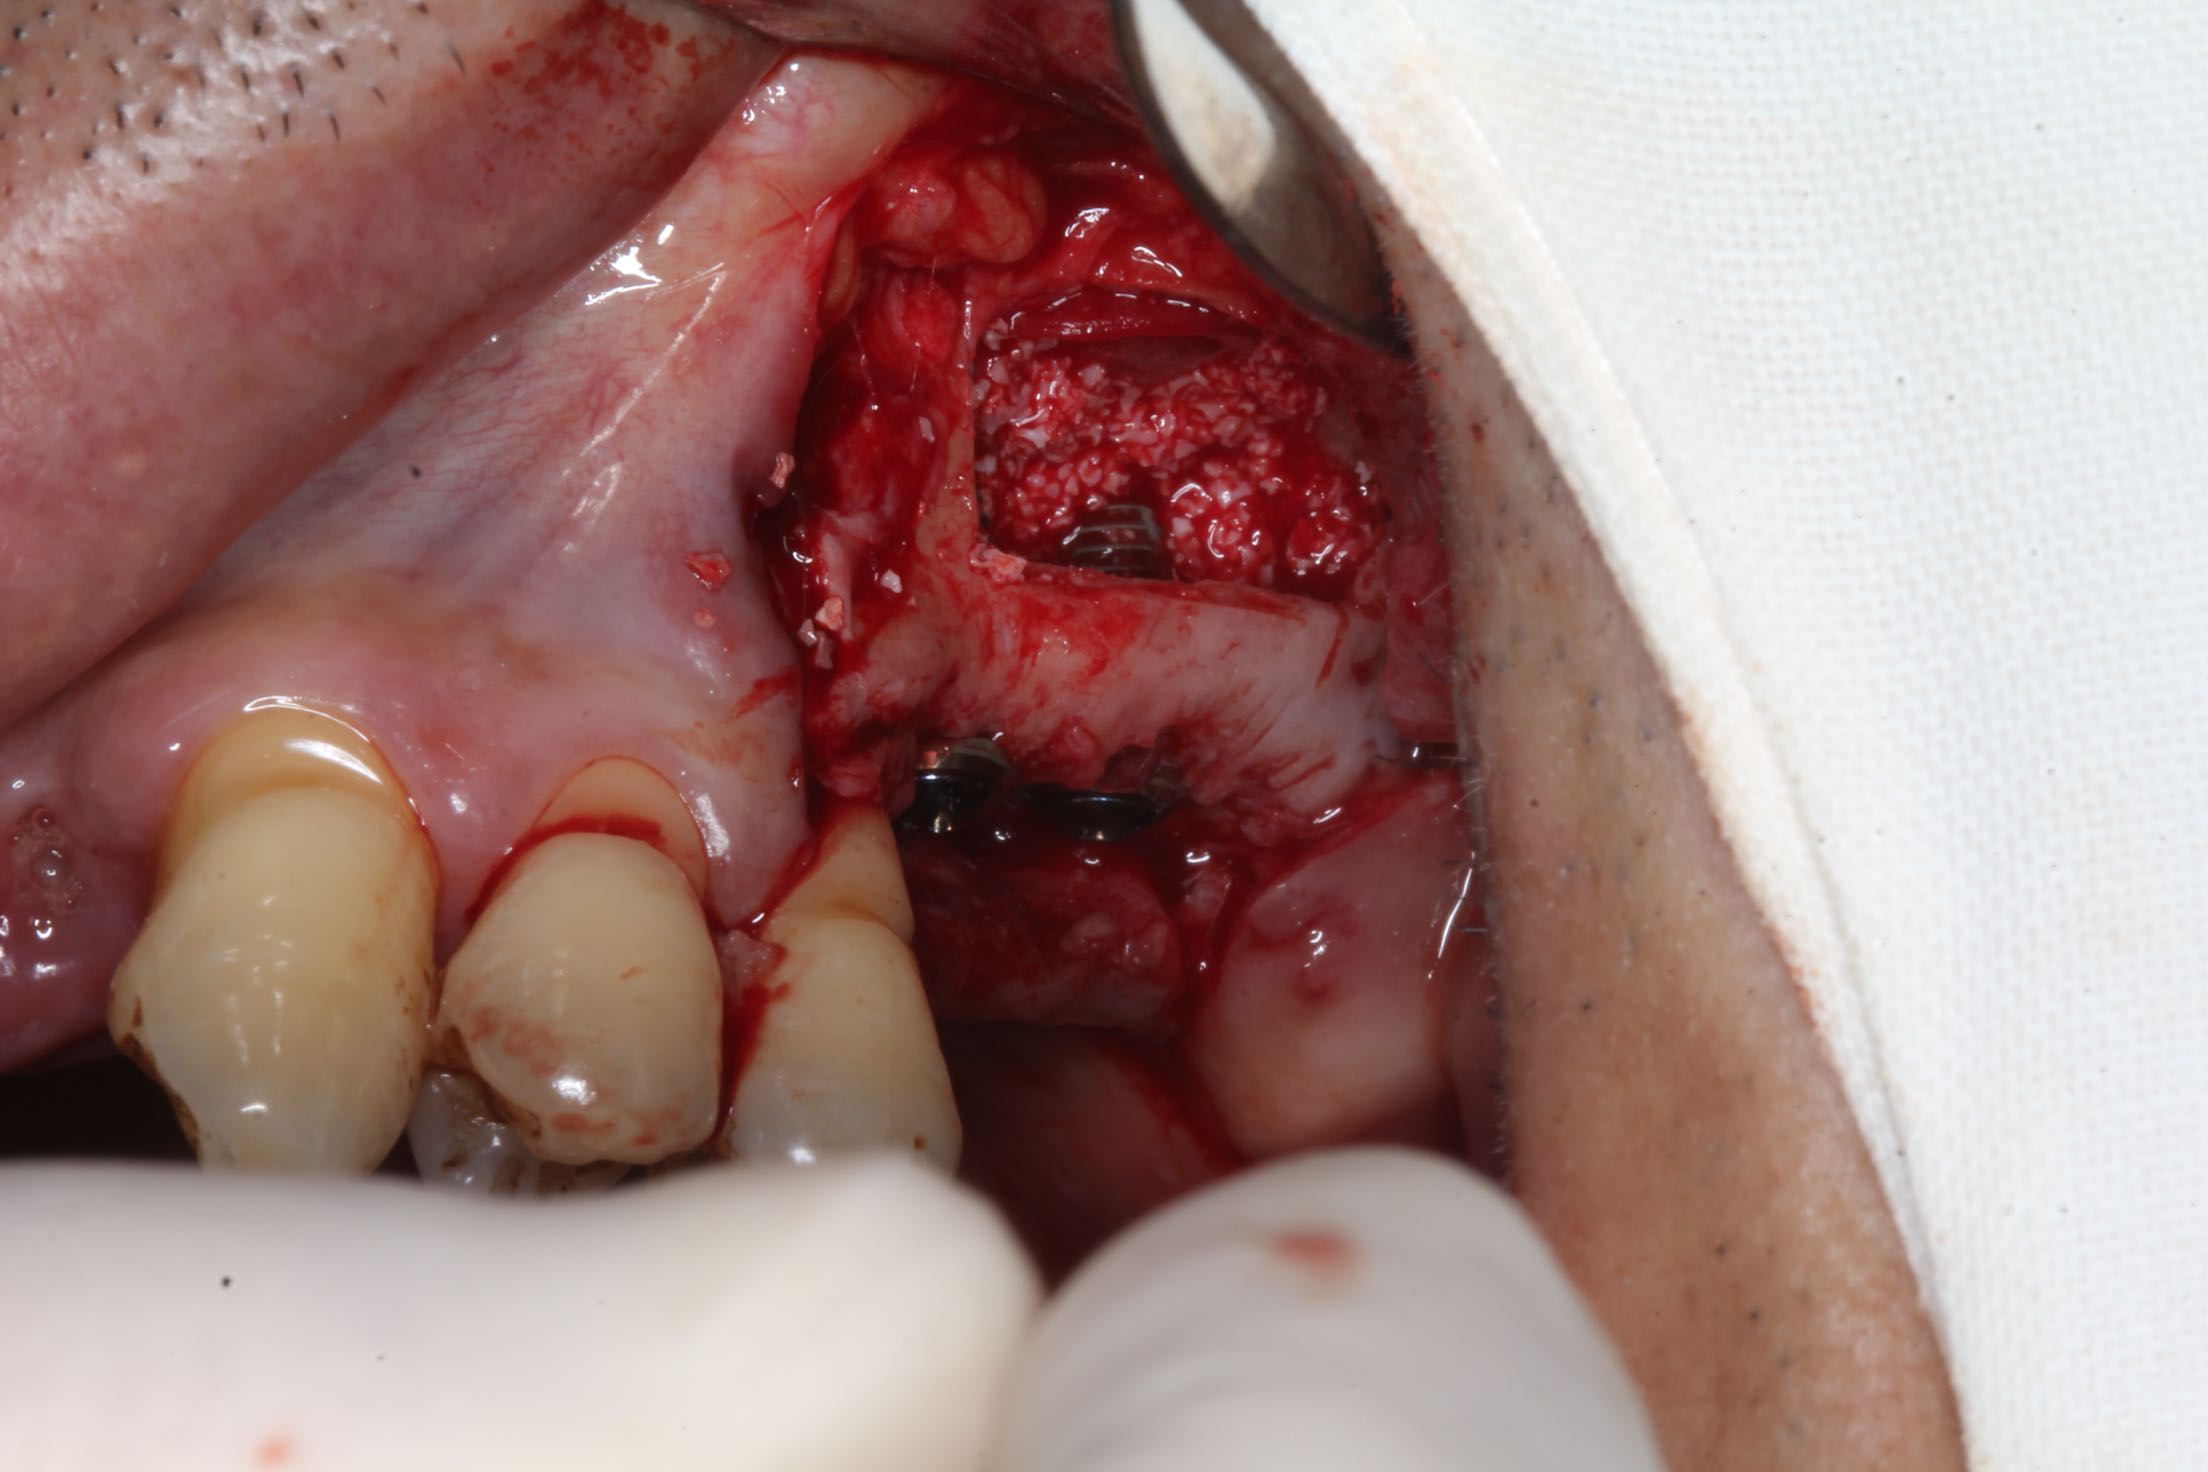

26、27缺失,牙槽骨严重吸收。 治疗:上颌窦外侧壁超刀开窗,取出外侧壁骨块,剥离黏膜,考虑严重吸烟史,黏膜菲薄,垫上一层胶原膜,植入部分Bio-ss骨粉,牙槽嵴顶备洞,26牙植入dentium4.3-10,27牙植入4.3-8,继续植入骨粉共0.5g,开窗处复原骨块,严密缝合!26牙植入扭力35牛,27植入扭力15牛!嘱尽量戒烟,